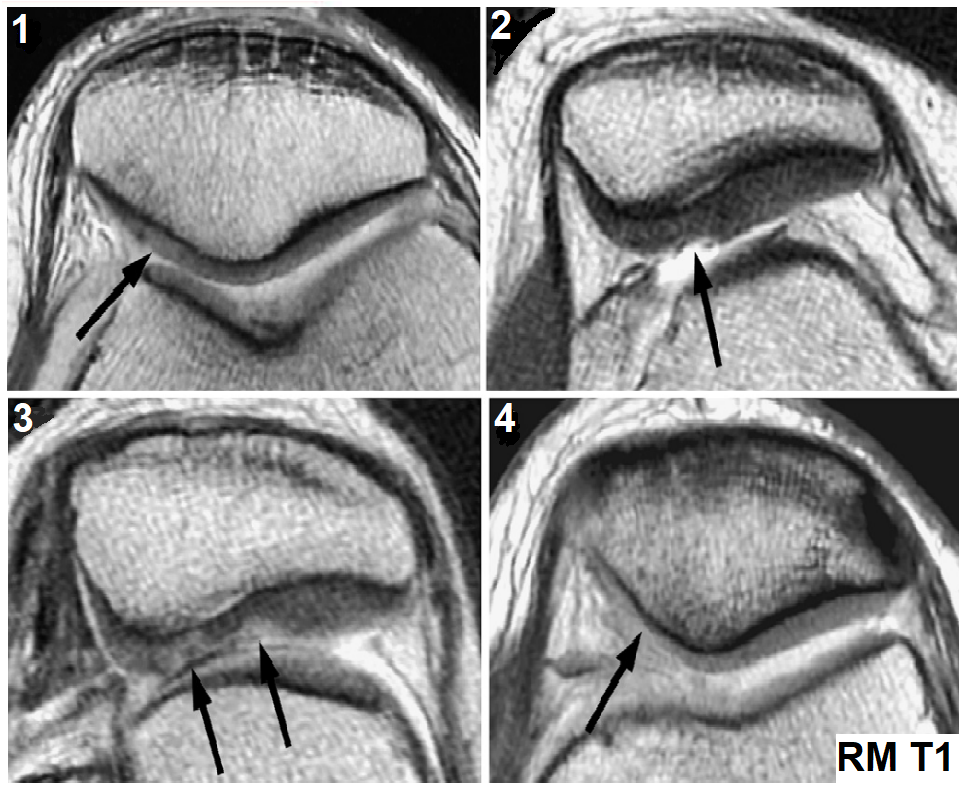

El desarrollo de esta patología es progresivo, por lo que presenta cambios degenerativos distintos en cada etapa de su desarrollo. Las etapas que nombraremos a continuación pueden ser detalladas a través de estudios de imagen como la resonancia magnética: